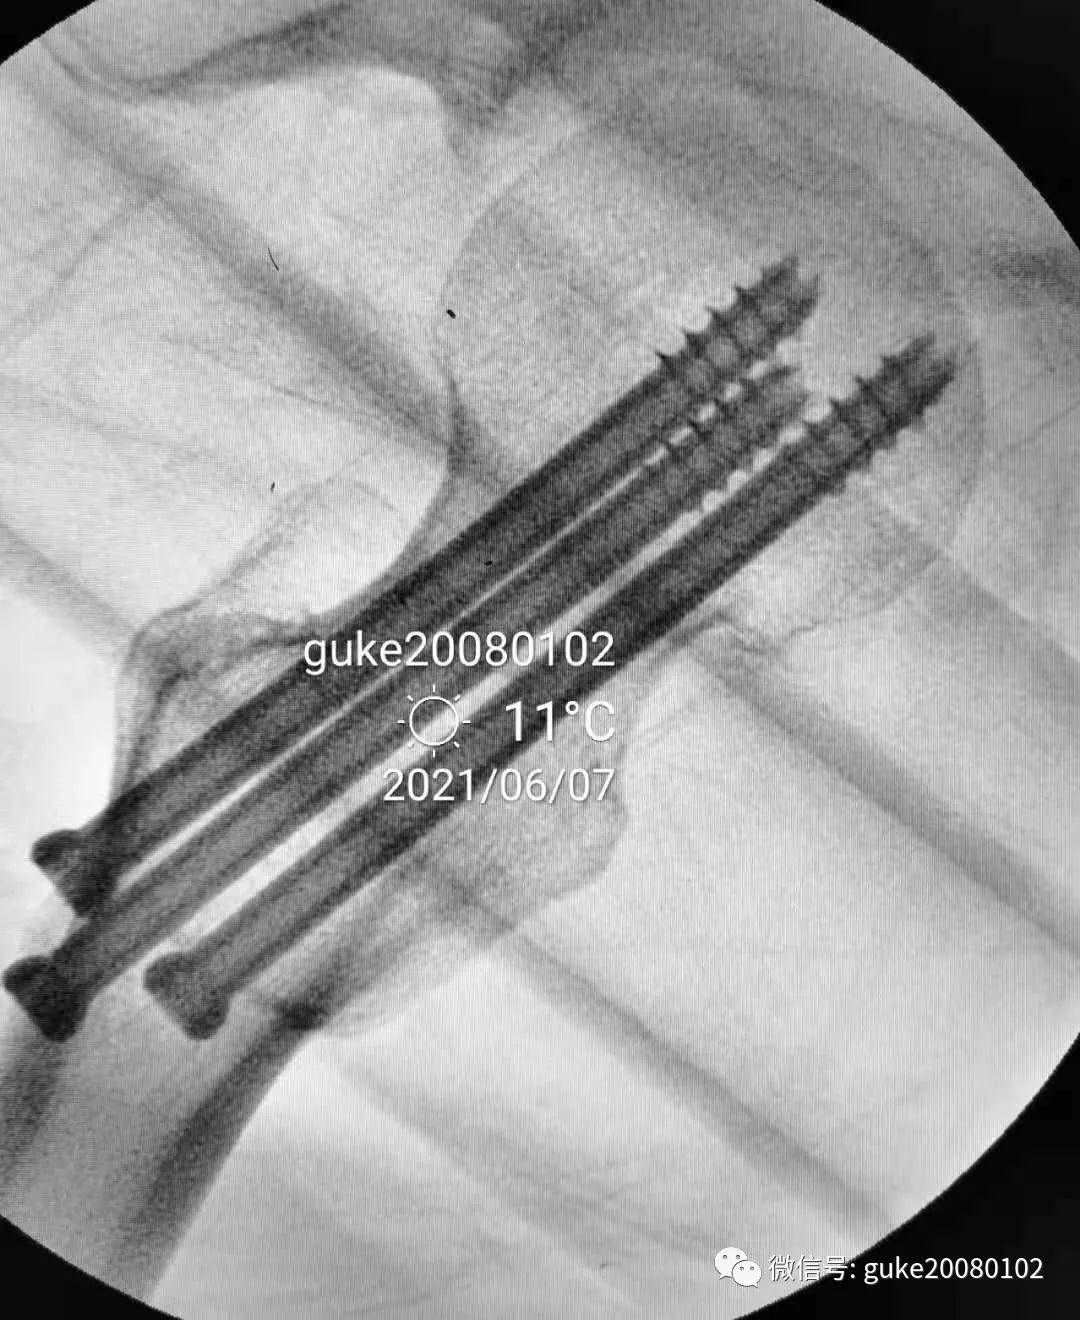

- 在大转子顶点近端5厘米处,经皮向股骨头上方插入直径2.0mm克氏针两枚,敲击克氏针至骨质,撬拨头颈骨折块复位。

- 撬拨力量偏小,骨折复位不足。再插入一枚2.5mm克氏针,接力撬拨,骨折复位。

1.正侧位观察骨折复位,骨小梁走形恢复。崁插骨折复位。

2.外侧植入克氏针一枚,临时固定骨折。

1、植入的第一枚克氏针,前倾和颈干角均满意。将其作为标志针。

2、植入第二枚导针,调整前倾和颈干角。

3、数次调整三枚导针到最合适的位置。

1.顺导针切开皮肤后,空心钻大转子外侧壁开口。

2.拧入三枚直径7.3mm空心钉,并逐步加压,稳定骨折断端。